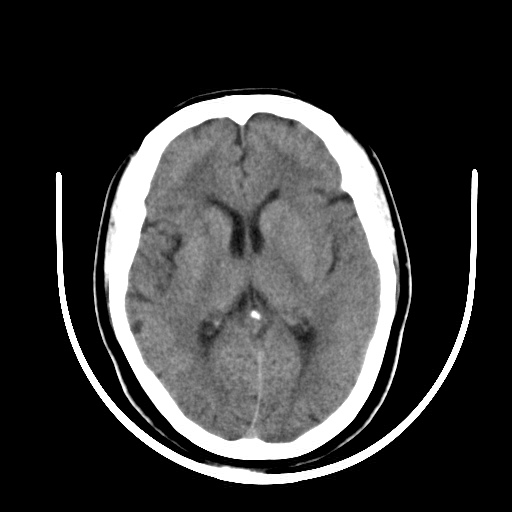

标题: CT16579:女 65岁间断性抽搐. [打印本页]

标题: CT16579:女 65岁间断性抽搐.

考虑右侧颞叶脑软化灶并脑穿通畸形;建议必要时行进一步检查。

右侧蛛网膜囊肿

右颞叶脑软化灶。余未见明显异常。

考虑右颞叶脑软化灶

右颞叶软化灶,右基底节区腔隙性脑梗塞;